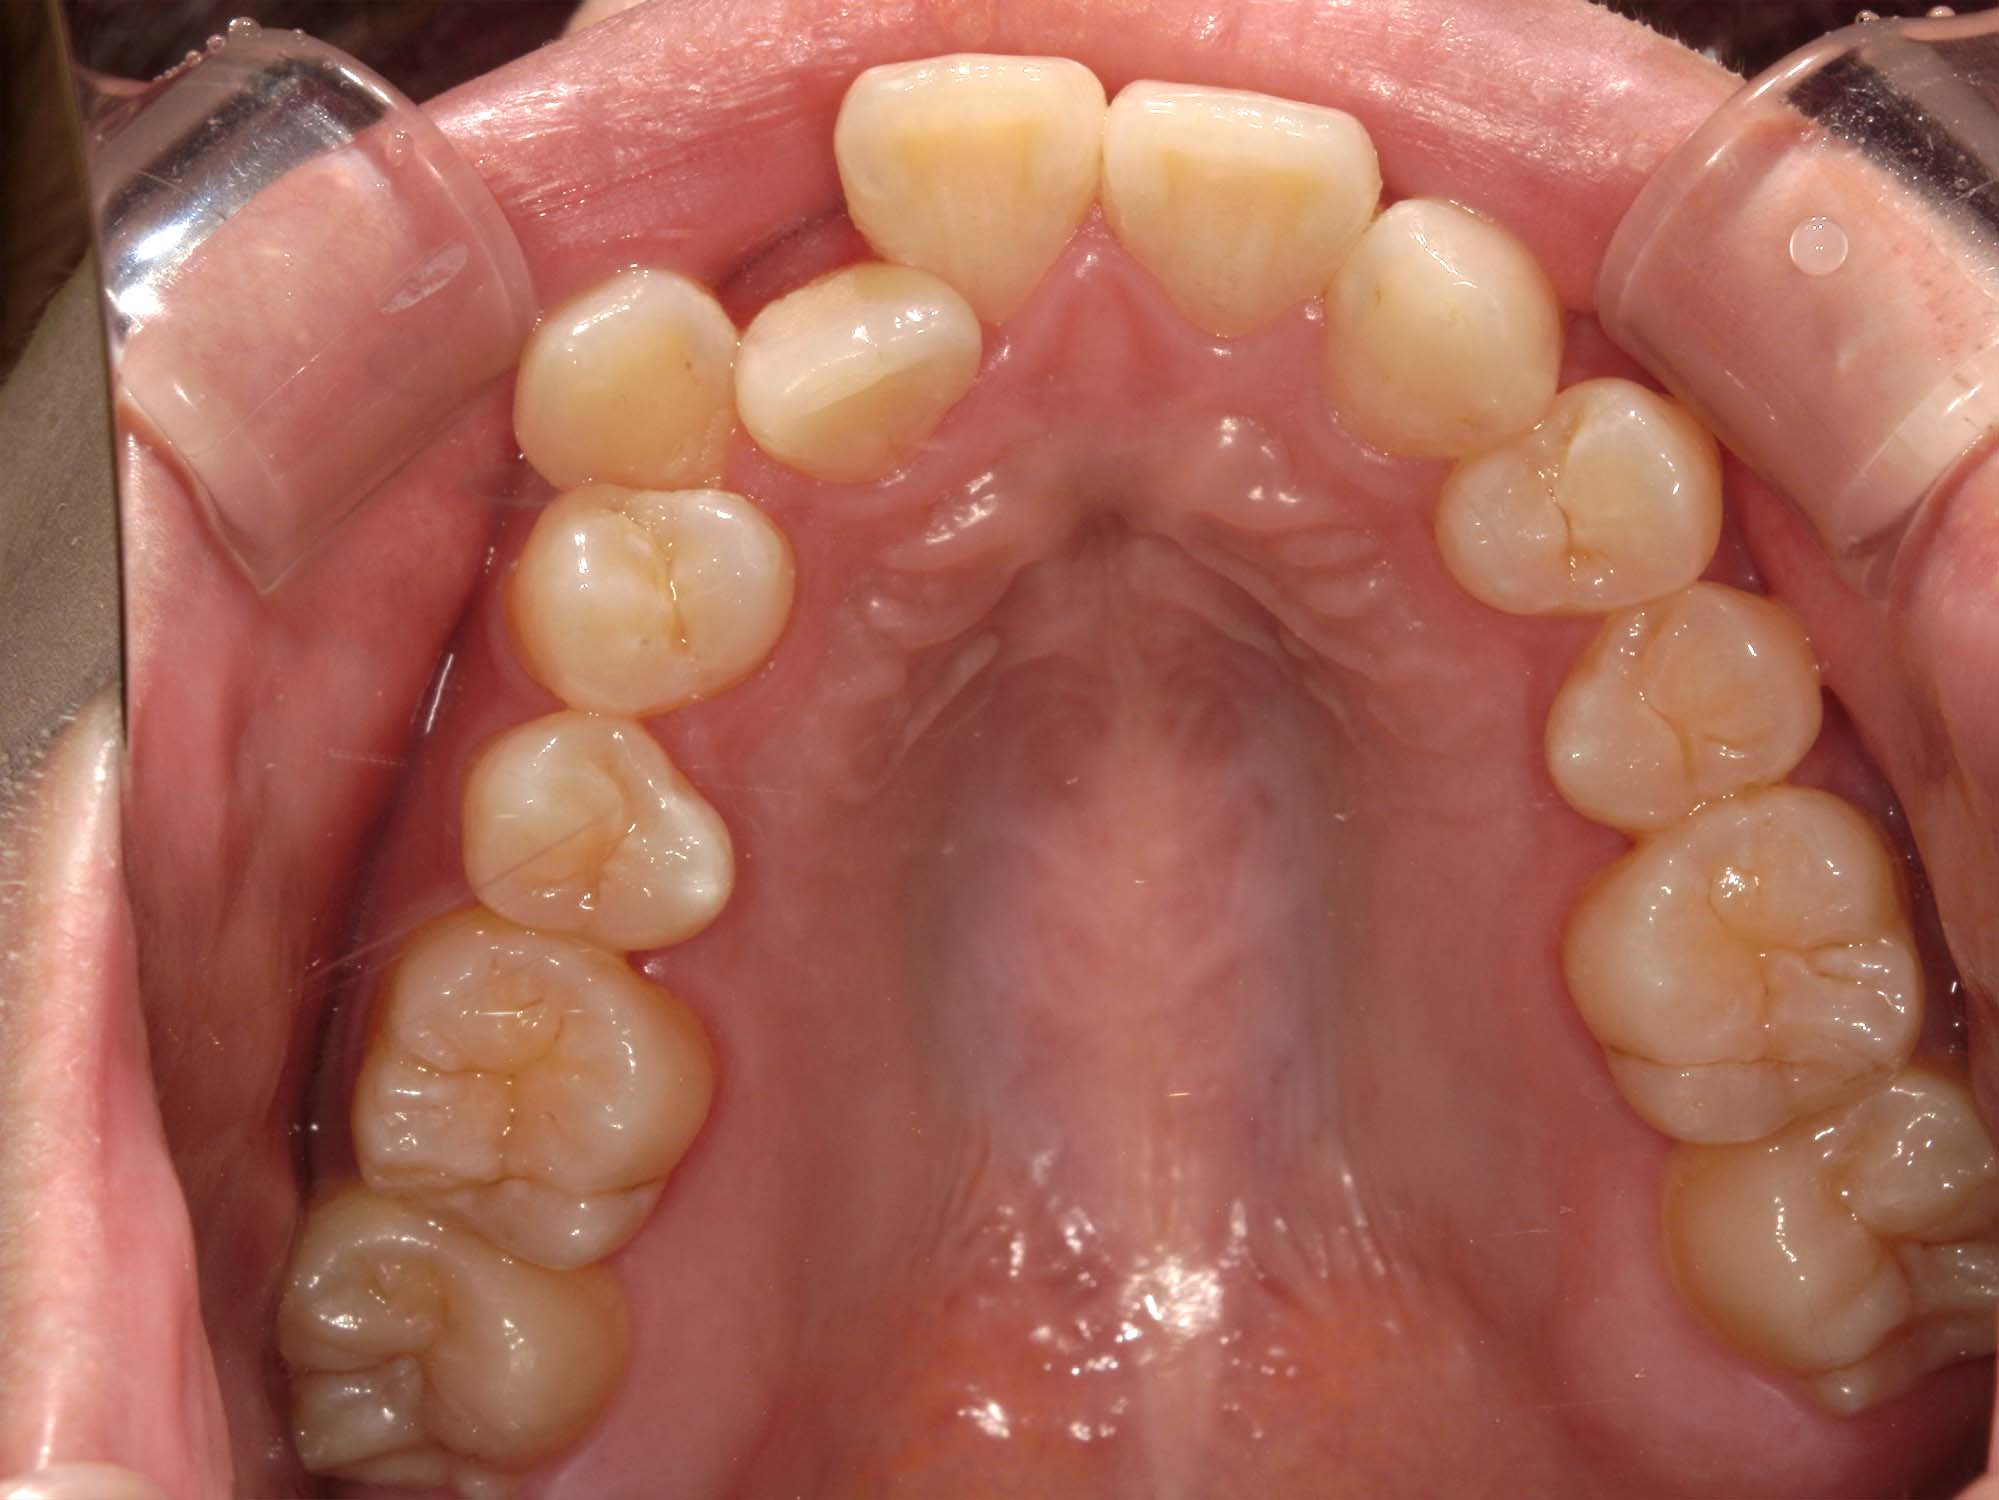

| 年齢・性別 | – |

|---|---|

| 主訴 | 叢生が気になる |

| 治療期間・回数 | 1年9ヶ月 |

| 費用 | 1,011,000円 |